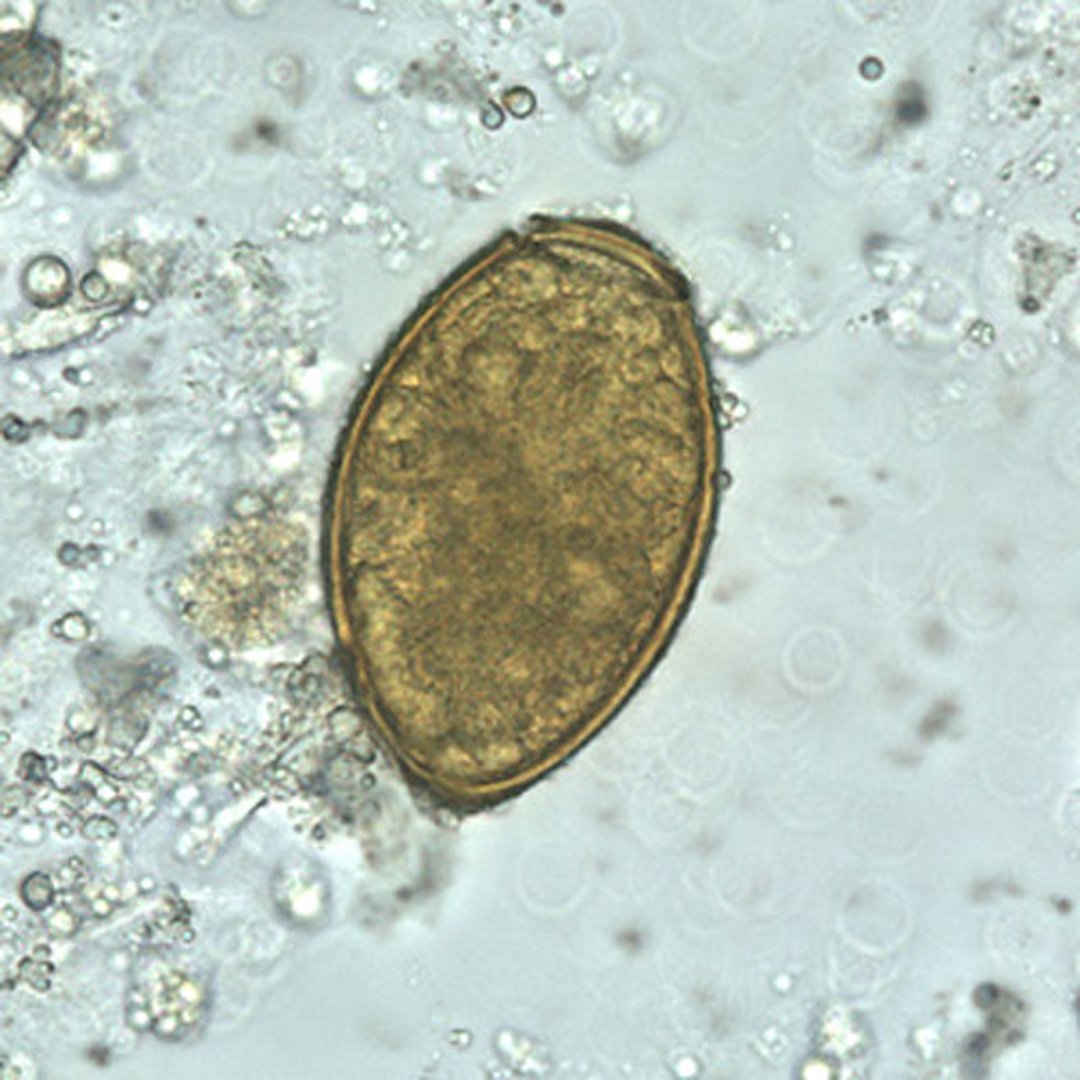

Les œufs de P. westermani varient de 80 à 120 micromètres de long sur 45 à 70 micromètres de large. Ils sont jaune-brun, ovoïdes ou allongés, et ont une coquille épaisse. Les œufs sont souvent asymétriques avec une extrémité légèrement aplatie. Au niveau de la grande extrémité, l'opercule est clairement visible. L'extrémité aboperculaire est épaissie.

Les œufs non embryonnés sont éliminés dans les crachats ou les selles.

CDC/DPDx